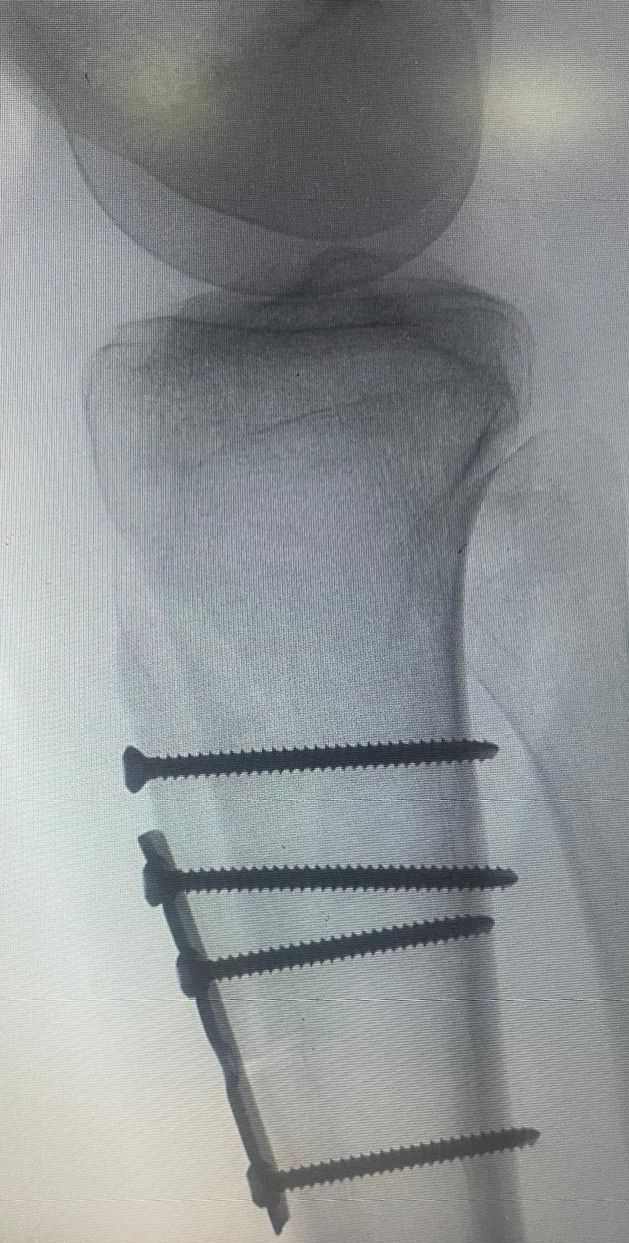

وتفصيلا قال الدكتور فهد الحليبي استشاري جراحة العظام والإصابات الرياضية المعقدة ، إن المريضة حضرت لمجمع  الدمام  الطبي وهي تعاني من خلع متكرر في عظمة الرضفة  بالركبة لعدة سنوات بالإضافة إلى اختلال ديناميكية أوتار الركبة، حيث تقرر إجراء عملية قص جذر وتر عظمة الرضفة وتغيير مسارها وتثبيتها جراحياً، إلى جانب إجراء تثبيت جانبي لنفس العظمة باستخدام وتر العضلة الخلفية بتقنية المنظار الجراحي.

وأكد " الحليبي " أن هذه الجراحة تُعد من العمليات النادرة في مجال جراحة العظام، حيث تتطلب خبرة ومهارة عاليتين، موضحاً أن مثل هذه الحالات كانت تُحول سابقاً إلى مراكز طبية خارج المنطقة ، مسلطا الضوء على التطور الكبير الذي حققه مجمع  الدمام  الطبي في مجال جراحة العظام.